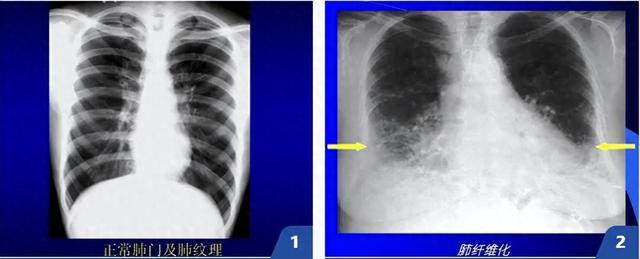

肺纤维化属于一种致命且无法治愈的间质性肺病。当肺组织反复受损后,异常修复过程使正常的肺泡结构逐渐被坚硬的瘢痕组织取代,就像被一层水泥牢牢包裹,使患者每次呼吸都格外艰难。

正常的肺像一块富有弹性的海绵,而纤维化后,肺组织变得像丝瓜瓤或蜂窝,无法有效扩张和回缩。患者会面临持续性干咳、活动后呼吸困难,严重时静息状态也会窒息。